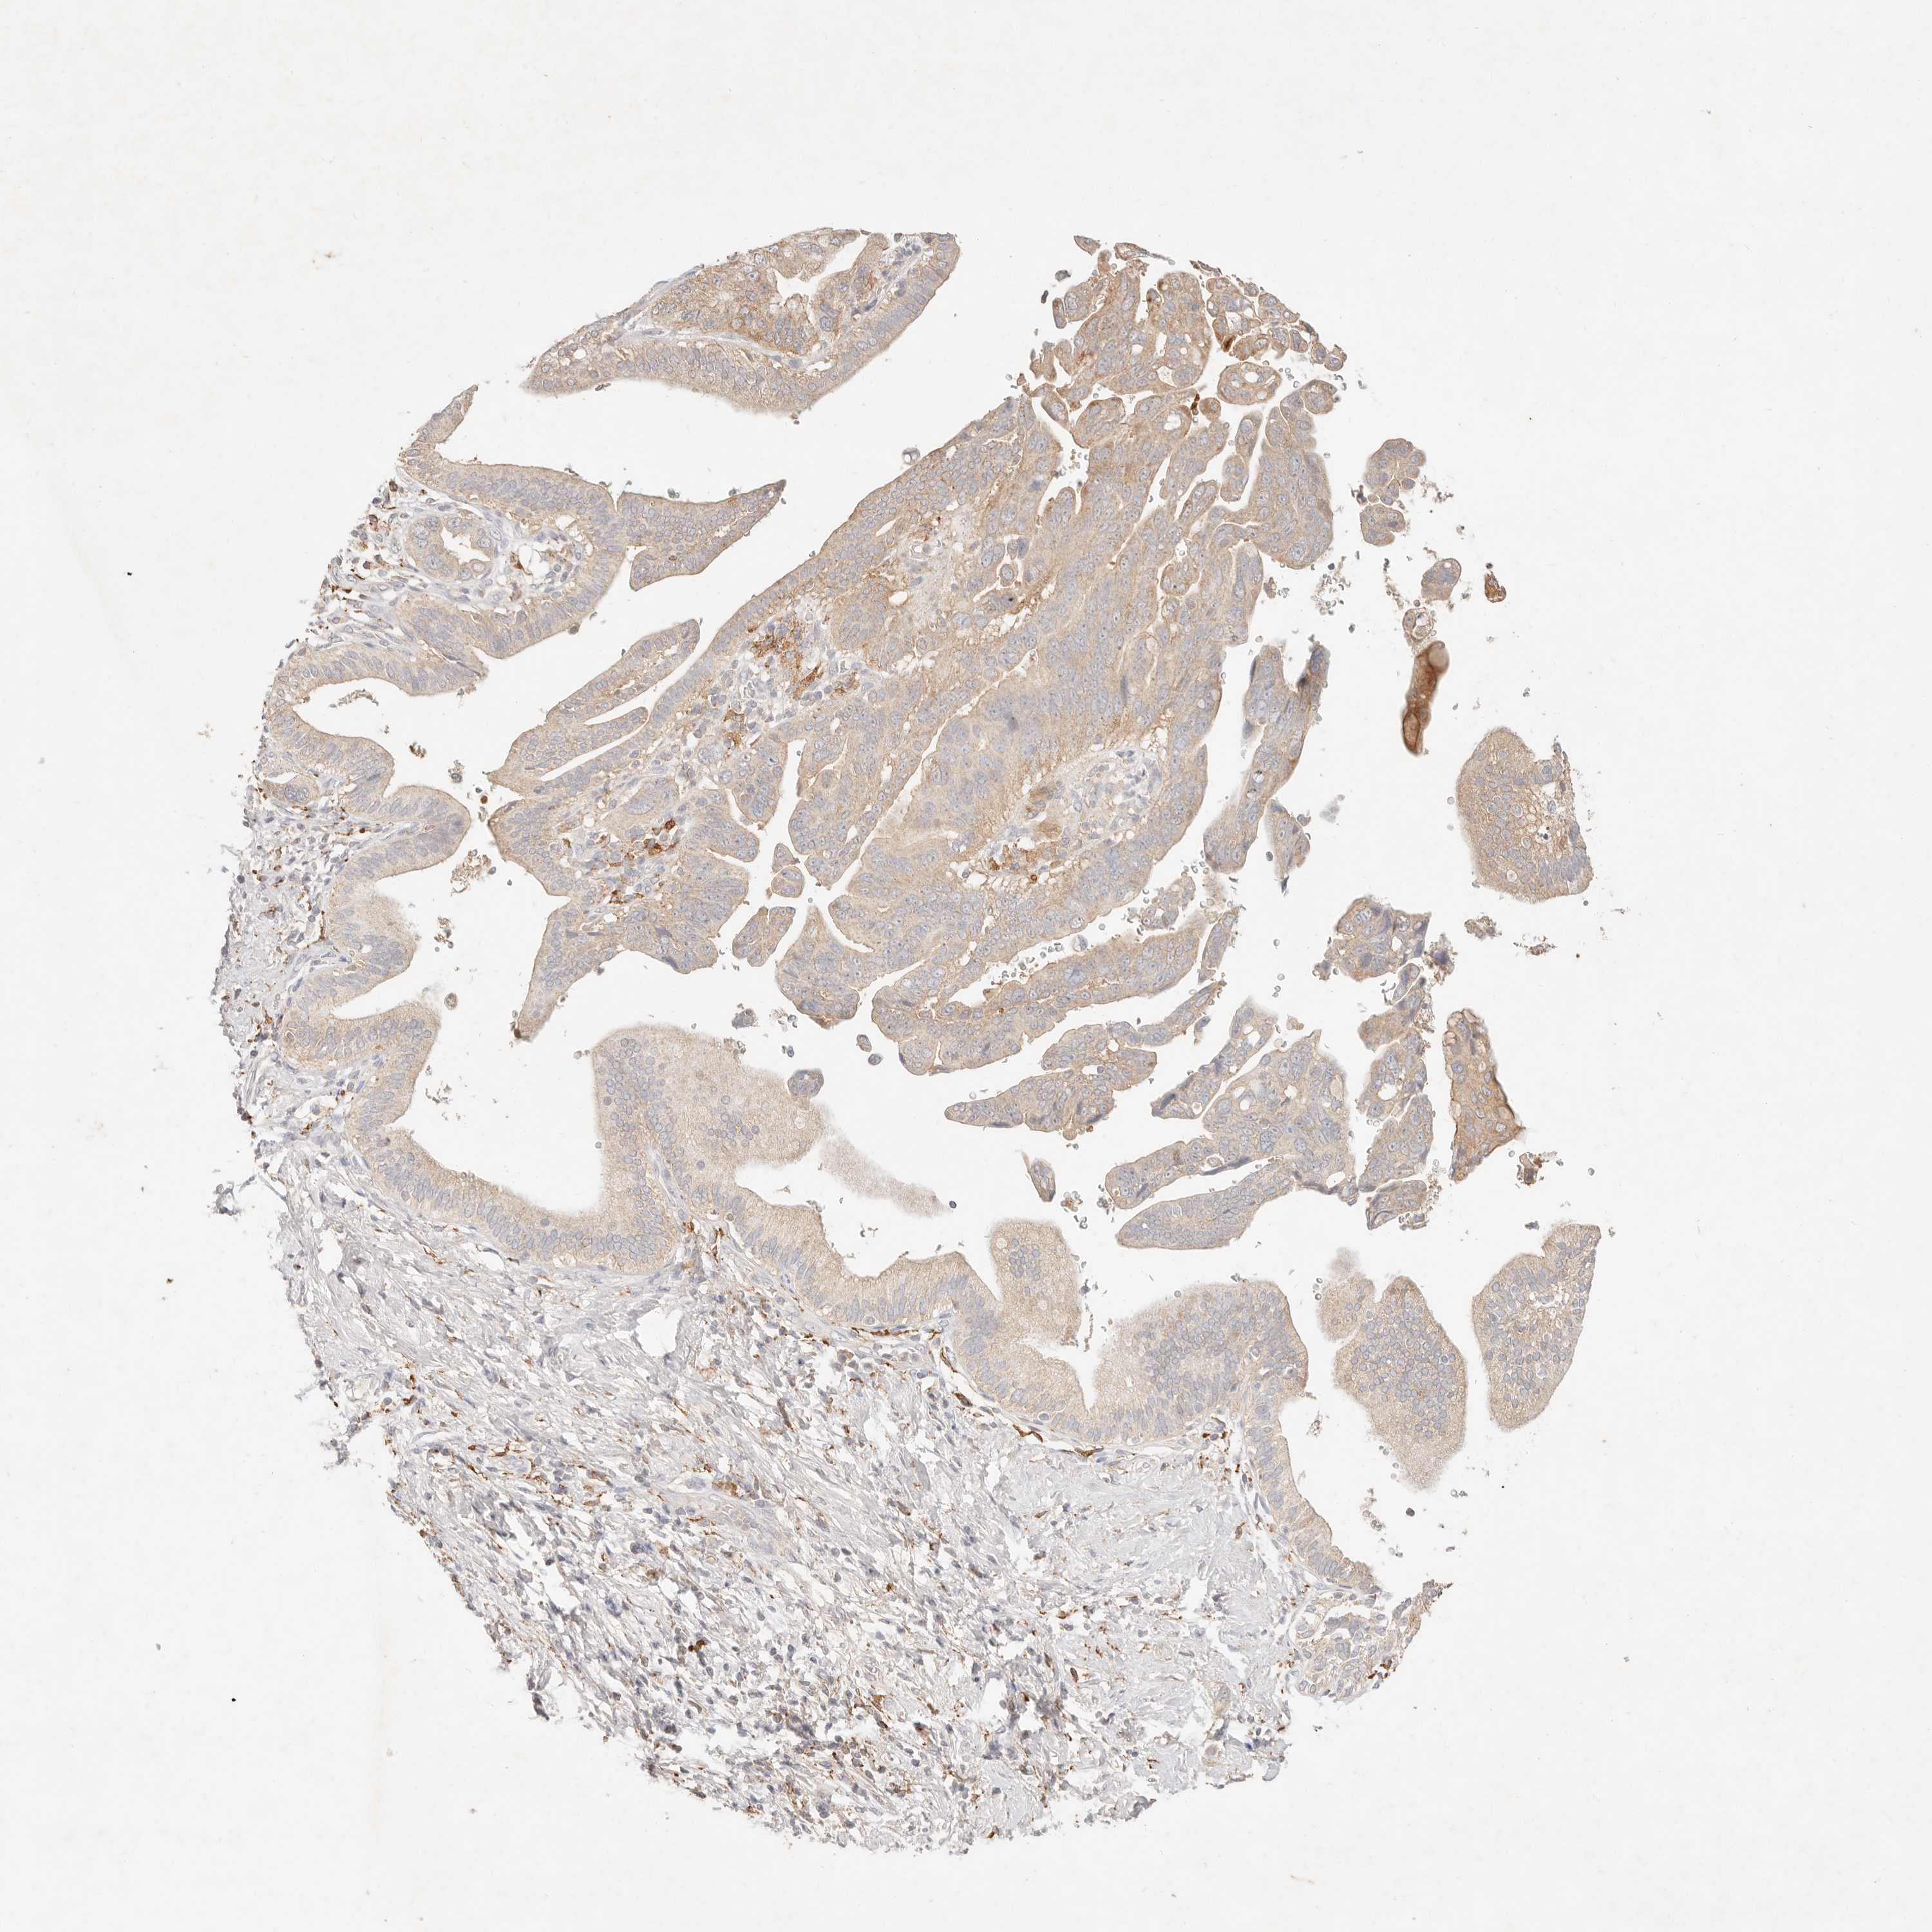

PANCREATIC CANCER - Protein expressioni

A mouse-over function shows sample information and annotation data. Click on an image to view it in a full screen mode. Samples can be filtered based on level of antibody staining by selecting one or several of the following categories: high, medium, low and not detected. The assay and annotation is described here.

Note that samples used for immunohistochemistry by the Human Protein Atlas do not correspond to samples in the TCGA dataset.

Antibody stainingi

Antibody staining in the annotated cell types in the current human tissue is reported as not detected, low, medium, or high, based on conventional immunohistochemistry profiling in selected tissues. This score is based on the combination of the staining intensity and fraction of stained cells.

Each image is clickable and will lead to virtual microscopy that enables deeper exploration of all samples and also displays staining intensity scores, fraction scores and subcellular localization as well as patient and tissue information for each sample.

Antibody HPA028587

Staining

High

Medium

Low

Not detected

Intensity

Strong

Moderate

Weak

Negative

Quantity

>75%

75%-25%

<25%

None

Location

Nuclear

Cytoplasmic/membranous

Cytoplasmic/membranous,nuclear

Adenocarcinoma, NOS